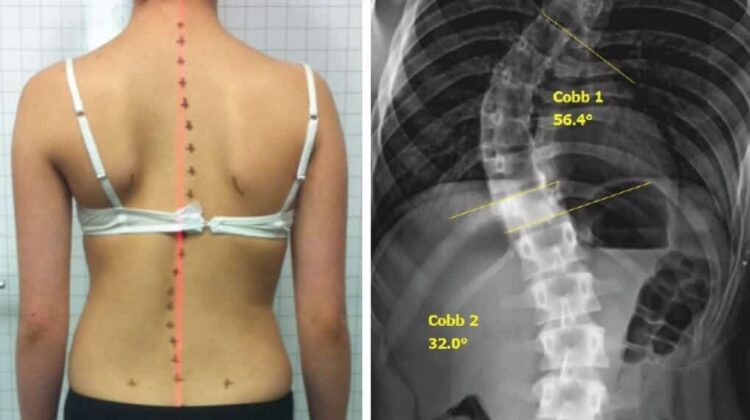

يشير مصطلح زاوية كوب (Cobb Angle) إلى المقياس الطبي الأساسي المستخدم لتحديد شدة اعوجاج العمود الفقري (الجنف). وعندما تكون زاوية كوب مرتفعة، فإن ذلك يعني أن الانحناء في العمود الفقري كبير وقد يكون له تأثيرات صحية ووظيفية مهمة، خاصة عند الأطفال والمراهقين في مراحل النمو. هذا المقال يشرح بلغة عربية فصحى مبسطة ما معنى زاوية كوب المرتفعة، ولماذا تهم المريض والأهل، وكيف تؤثر على التشخيص والعلاج.

زاوية كوب هي طريقة قياس تُستخدم في صور الأشعة السينية لتحديد درجة انحناء العمود الفقري.

يقوم الطبيب برسم خطين على الفقرات الأكثر ميلًا في أعلى وأسفل الانحناء، ثم يحسب الزاوية بينهما. هذه الزاوية هي التي تحدد شدة الجنف.

عادةً يتم تصنيف زاوية كوب كالتالي:

أقل من 10 درجات: لا يُعتبر جنفًا حقيقيًا

من 10 إلى 20 درجة: جنف خفيف

من 20 إلى 40 درجة: جنف متوسط

أكثر من 40–50 درجة: جنف شديد

عندما تتجاوز زاوية كوب 40 أو 50 درجة، يبدأ القلق الطبي الحقيقي، لأن الانحناء قد يستمر في التفاقم ويؤثر على وظائف الجسم.